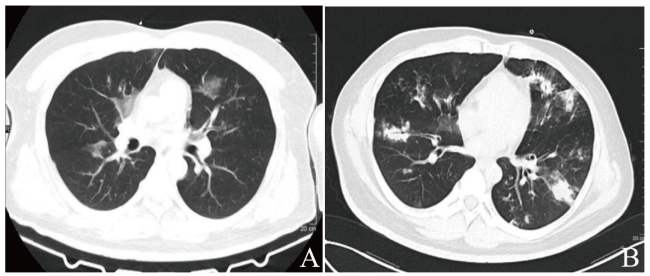

实验室及辅助检查:尿常规示酮体(++++),葡萄糖(++++)。随机静脉血糖17.16 mmol/L。动脉血气分析示酸碱度7.047,氧分压66.8 mmHg,二氧化碳分压23.4 mmHg,阴离子间隙24.4 mmol/L,碳酸氢根离子6.4 mmol/L。血常规示血红蛋白164 g/L,红细胞5.65×1012/L,白细胞16.87×109/L,中性粒细胞绝对值14.63×109/L,淋巴细胞绝对值0.74×109/L,血小板233×109/L。血液生化示肝肾功能无异常。血钾4.96 mmol/L、钠133 mmol/L、镁0.96 mmol/L、磷1.19 mmol/L(参考值范围0.8~1.5 mmol/L)、钙2.21 mmol/L。GHbA1c 12.7%。甲状腺功能提示低T3综合征。肿瘤标志物、肥达外斐反应、风湿免疫相关检查均无异常。心电图示窦性心动过速。头颅CT未见异常。肺部CT示双肺散在渗出,见图1A。肺动脉造影CT血管成像未见明显栓塞。腹部CT示胰腺萎缩、胰头部点状钙化,胆囊多发结石、慢性胆囊炎。痰涂片仅检出少量革兰阳性球菌,2次痰培养、3次血培养、中段尿培养、乙型流感病毒RNA、疟原虫等均阴性,腹部B超提示脂肪肝及胆囊结石。初步诊断:①DKA;②肺部感染。

图1 一例DKA合并低磷血症、烟曲霉菌肺炎患者的CT检查图

注:A为2022年3月18日肺部CT表现;B为2022年3月28日复查肺部CT表现。